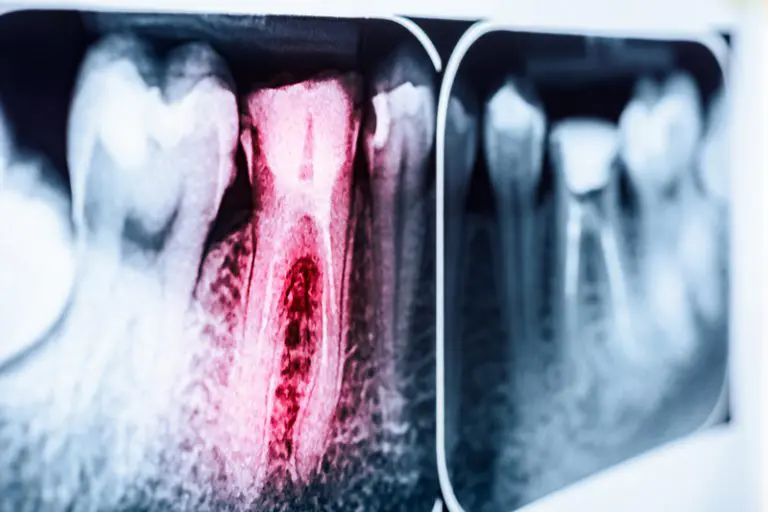

- Evaluación inicial y diagnóstico: Se realiza un examen clínico y radiografías para determinar el estado del diente y la necesidad del tratamiento.

Tecnología avanzada: Utilizamos radiología digital y otros equipos de última generación para un diagnóstico preciso.